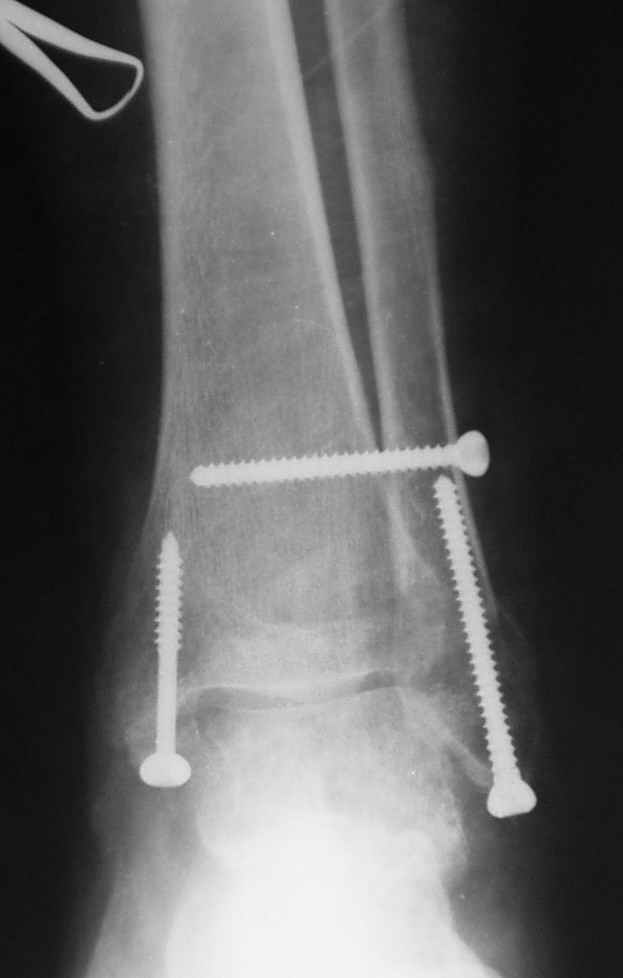

Ниже рентгенограммы

До операции 28 июля

Операция 29 июля

Через месяц

Боковой через месяц

15 ноября прямой

15 ноября боковой

15 ноября трехчетвертной

12 января прямой

12 января боковой

12 января трехчетвертной

Риторический вопрос - в каком руководстве рекомендован такой способ остеосинтеза наружной лодыжки?

Очевидно, такой результат операции был запрограммирован. При невосстановленной длине и практически нефиксированной малоберцовой кости (этот кортикальный винт - как карандаш в стакане), при неустраненном подвывихе, невправленной и тоже нефиксированной внутренней лодыжке нет стабильной вилки сустава. Если такую операцию сделать даже сразу, а не через 4 месяца, то результат ожидаем

тот же.

Вообще говоря, такое повреждение вполне успешно можно лечить без операции - если 6 недель подержать в гипсовом "сапожке" с хорошо устраненным подвывихом. Вероятное несращение внутренней лодыжки не обязательно компрометирует результат.

Ну а уж если выбран остеосинтез - нначать надо было с репозиции малоберцовой кости с точным восстановлением длины, с фиксацией треть-трубчатой пластиной по задней поверхности. Позиционный винт

избыточен - повреждение практически подсиндесмозное. А если бы

действительно было повреждение синдесмоза - в 4 месяца позиционный винт - не решение. Внутренню лодыжку такую - надо было бы спицами и проволочной петлей. Извините за эти банальности.

Вариант с артродезом уже обсудили. Хотя, после увиденых снимков, пессимизм насчет восстановительной операции у меня, например, несколько уменьшился. Особенного уж какого-то остеопороза не видно даже на январских снимках. Можно черед мини-доступы убрать винты, аппаратом вправить малоберцовую кость, устранить подвывих стопы. Ну а дальше фиксировать малоберцовую пластиной сзади. А может, и напряженной Y-спицей попробовать - Анатолий Федорович, как Вы полагаете? Внутреннюю - то, что осталось, если уже не получится сделать спицами и проволокой, то что-то типа пластики дельтовидной связки. А может, и не трогать ее вовсе... В общем, выбор непростой,

много факторов надо взвесить.

Если до сих ничего не сделано, с артродезом сустава в данный момент я бы повременил, на выставленных январских снимках хорошо сохранившийся сустав, а в "мортиз" (трехчетвертной) и на боковых снимках не менее 5 мм укорочение малоберцовой кости. Косые переломы лучше фиксировать пластинами, как то мы разбирали случай, где было отмечено, что это закон "таранная кость всегда следует за малоберцовой".

В данном случаи я бы уговорил больного на реконструкцию, для этого после удаления шурупов, спереди очистить от рубцов синдесмоз, несросшуюся наружную лодыжку - остеотомия по линии перелома и компрессирующий (lagging technique) кортикальный шуруп 3.5 мм по поперечнику остеотомии. Следующий этап - восстановление длины малоберцовой за счет удлинения, сделать поперечную остеотомию где-то на уровне сантиметр выше вашего синдесмозного шурупа, наложить длинную пластинку, прикрепить пластину за дистальный конец двумя или тремя шурупами; сохраняя контакт пластины с костью, имеющимся

compression&tension device AO system (при отсутствии любой lamina spreader подойдет, создать дистанцию между пластиной и шурупом, проведенным проксимальнее пластины) толкая проксимальный отдел пластины, низвести пластину, мортиз рентгенограмма подскажет на сколько. Если заранее сделать предоперационный план (ренгенограмма другой стороны), тогда точно можно определить, на сколько вам необходимо сделать поперечную остеотомию малоберцовой кости, для закрытия создавшегося дефекта.

Убедившись, что желаемая длина восстановлена, окончательная фиксация пластины, при этом через пластину пару 3.5 мм шурупов на синдесмоз, предпочтительно в четыре кортекса и оставить на 3 мм длиннее, если под нагрузкой синдесмотический шуруп сломается, сломанный конец легче удалить с медиальной стороны.

Медиальная сторона не в нагрузочной зоне, и там большая дыра - если есть 2.7 мм шурупы, или пару спиц в ваших условиях или методика Лазарева. Необходимо уделить внимание к мягким тканям, обнажается кость с латеральной стороны и у места где проводится остеотомия.